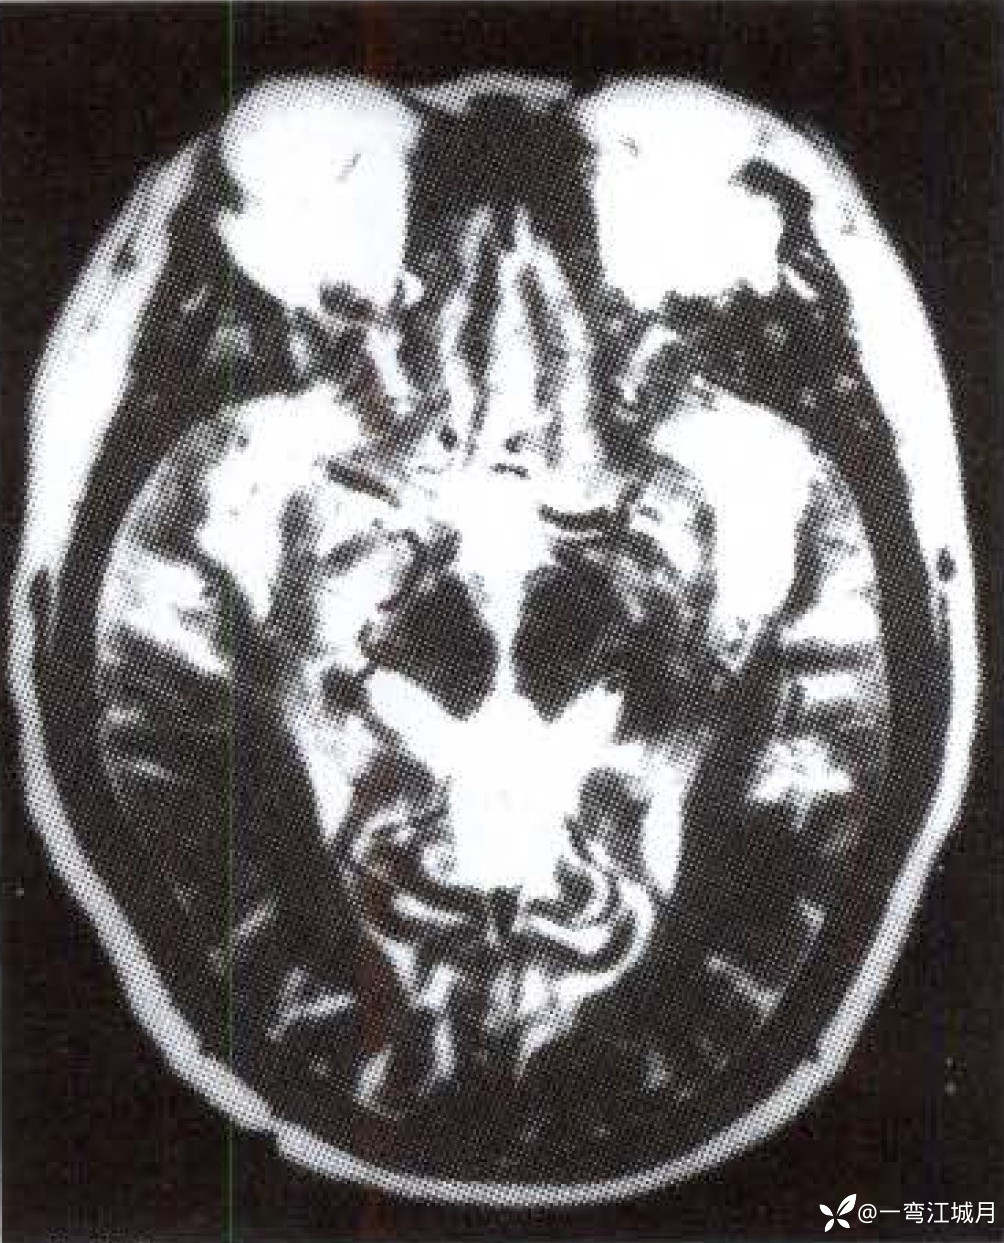

影像学征象:MRI T1WI(图1-A)示双侧大脑半球脑底内侧很多纤细、不规则的具有流空效应的点条状异常血管网。T2WI(图1-B)示脑底部、 Willis 环旁及侧裂池内许多迂曲的流空血管影;矢状面T2WI(图1- C , D )示脑底向上至大脑半球许多断续呈放射状分布的流空异常血管网及脑顶部许多小片状高信号梗死灶。右侧颈内动脉 DSA 示额顶区扇形广泛分布异常血管网。

本例需鉴别其为动静脉畸形或为 Moyamoya 病。本例 DSA 表现为颈内动脉床突上段、大脑前动脉及中动脉近段、基底动脉远段狭窄与闭塞,因此从脑底部向上呈放射状分布的迁曲流空血管影可解释为脑血管闭塞后脑底部形成丰富的侧支循环,穿越于脑膜、脑实质,形成脑底部异常血管网。当侧支循环不丰富时,其供血区可发生缺血性脑梗死。脑深部的动静脉畸形( AVM )于丘脑和基底节区也可见多发流空血管,但与本例的主要区别为:①本例有动脉狭窄闭塞,而 AVM 为供血动脉扩张增粗;②本例无 AVM 常见的粗大引流静脉:③本例血管影排列多为纵行条纹状, AVM 则方向无序。